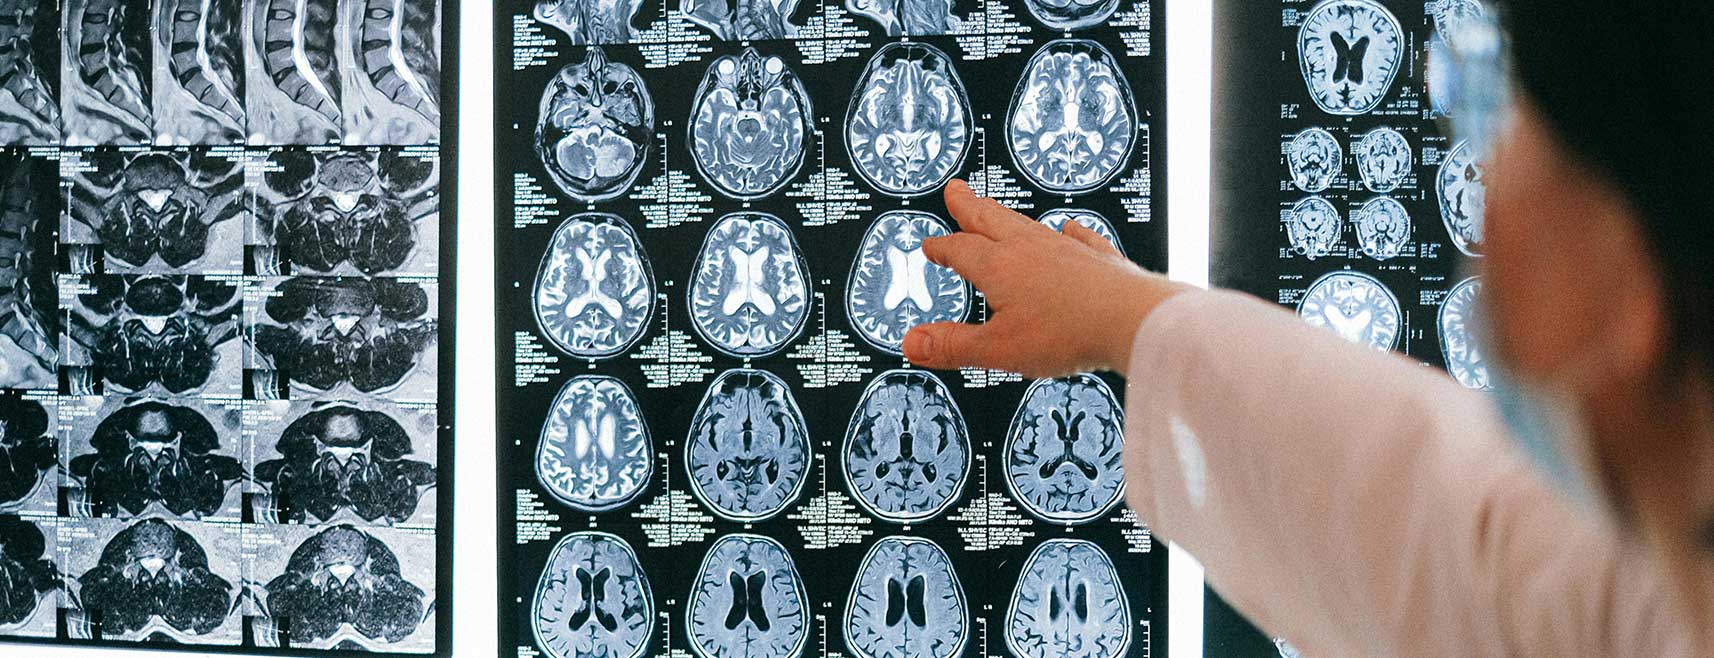

Enfermedades Neurológicas

• Cirugía de tumores cerebrales

• Tumores cerebrales